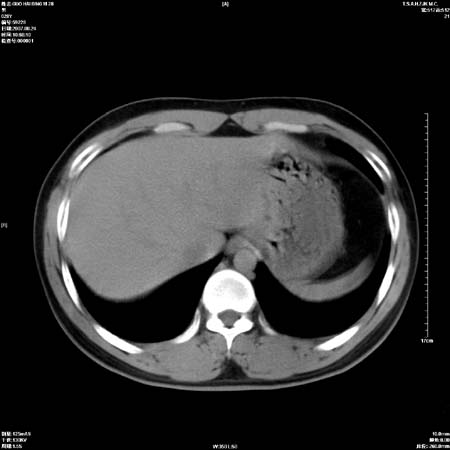

男性,28岁,体检发现左肺病变,患者只有背部隐痛感,哀哉,真不忍心下诊断啊。

直接下肺癌诊断还太早,病灶较大,估计5cm以上,但阻塞性改变及对临近纵隔及支气管侵犯不明显,密度较均匀,弓旁见一单个淋巴结,需要排除炎症性肿块及腺瘤,平滑肌瘤等。

左肺中心型肺癌并纵隔淋巴结转移!考虑为小细胞肺癌,没有手术机会了,只能进行放化了,疗效不错,但极易复发。没办法,现在肿瘤年轻化越来越明显了。